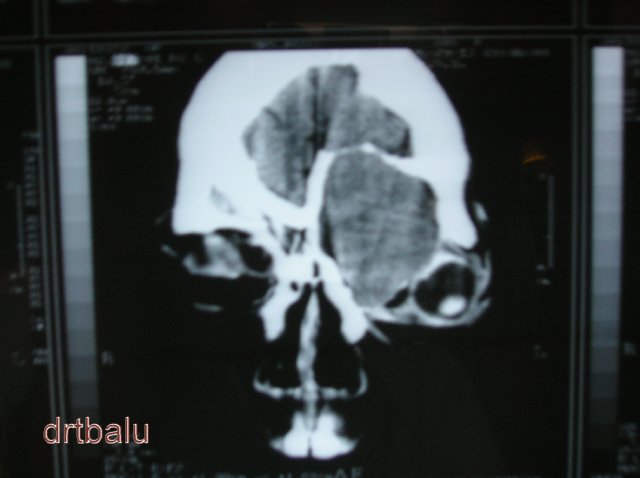

CT scan and MRI scan of the orbit may prove beneficial in diagnosing the cause for proptosis. The presence of fat in the orbit serves as an inherent contrast medium for the study. 3 mm cuts are ideal for the study of orbit. Ultrasound studies using either A or B mode may help in rapid diagnosis of the cause for proptosis.

Coronal CT image of nose and sinuses showing proptosis